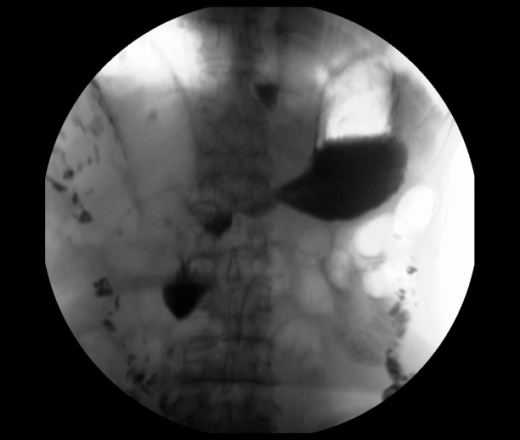

Мужчина 73 года. Жалобы на сниженный аппетит, слабость. Исследование выполенено через несколько дней после ирригоскопии. По результатам ЭФГДС гастрит.

Угол желудка развернут, ригиден. Стойкое циркулярное сужение антрального отдела.Перистальтики нет. Складки прослеживаются.

Эндофитный C-r антрального отдела.